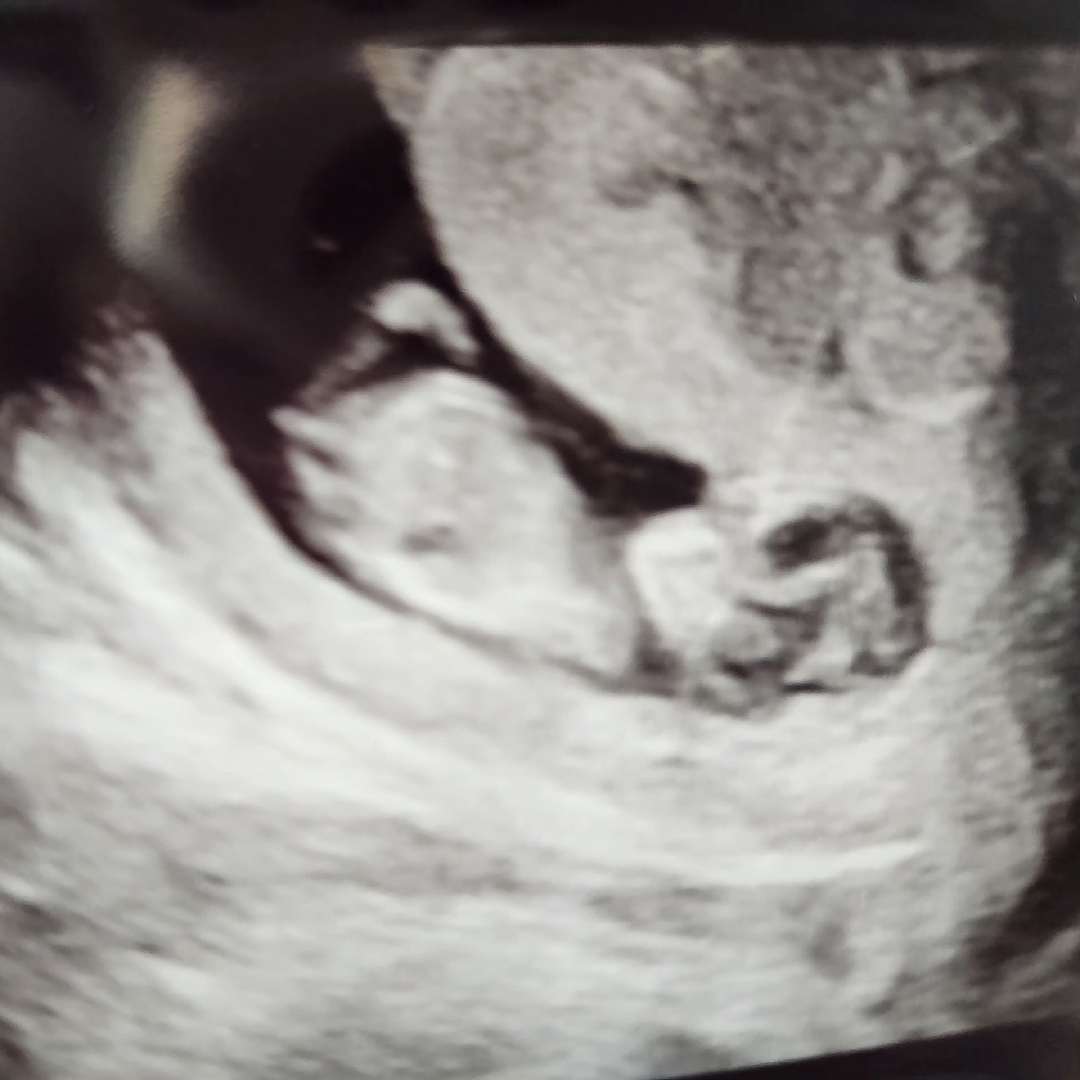

안녕하세요 11주2일이고 아기 크기는 4일입니당 첫아기라 다 너무 신기하고 벅찬데요 오늘 본 초음파로 각도법 볼수있을까요?? 제가보기엔 척추랑 평행해서 딸일까 싶은데 다들 어떻게 보이시나요? 물론 뭐든 다 귀엽겠지만 궁금은 하네요 ㅎㅎ 3주사이에 너무 많이 자라서 기특해요 ㅜ ㅜ

각도상으론 딸처럼 보여용

딸 같아보여용!